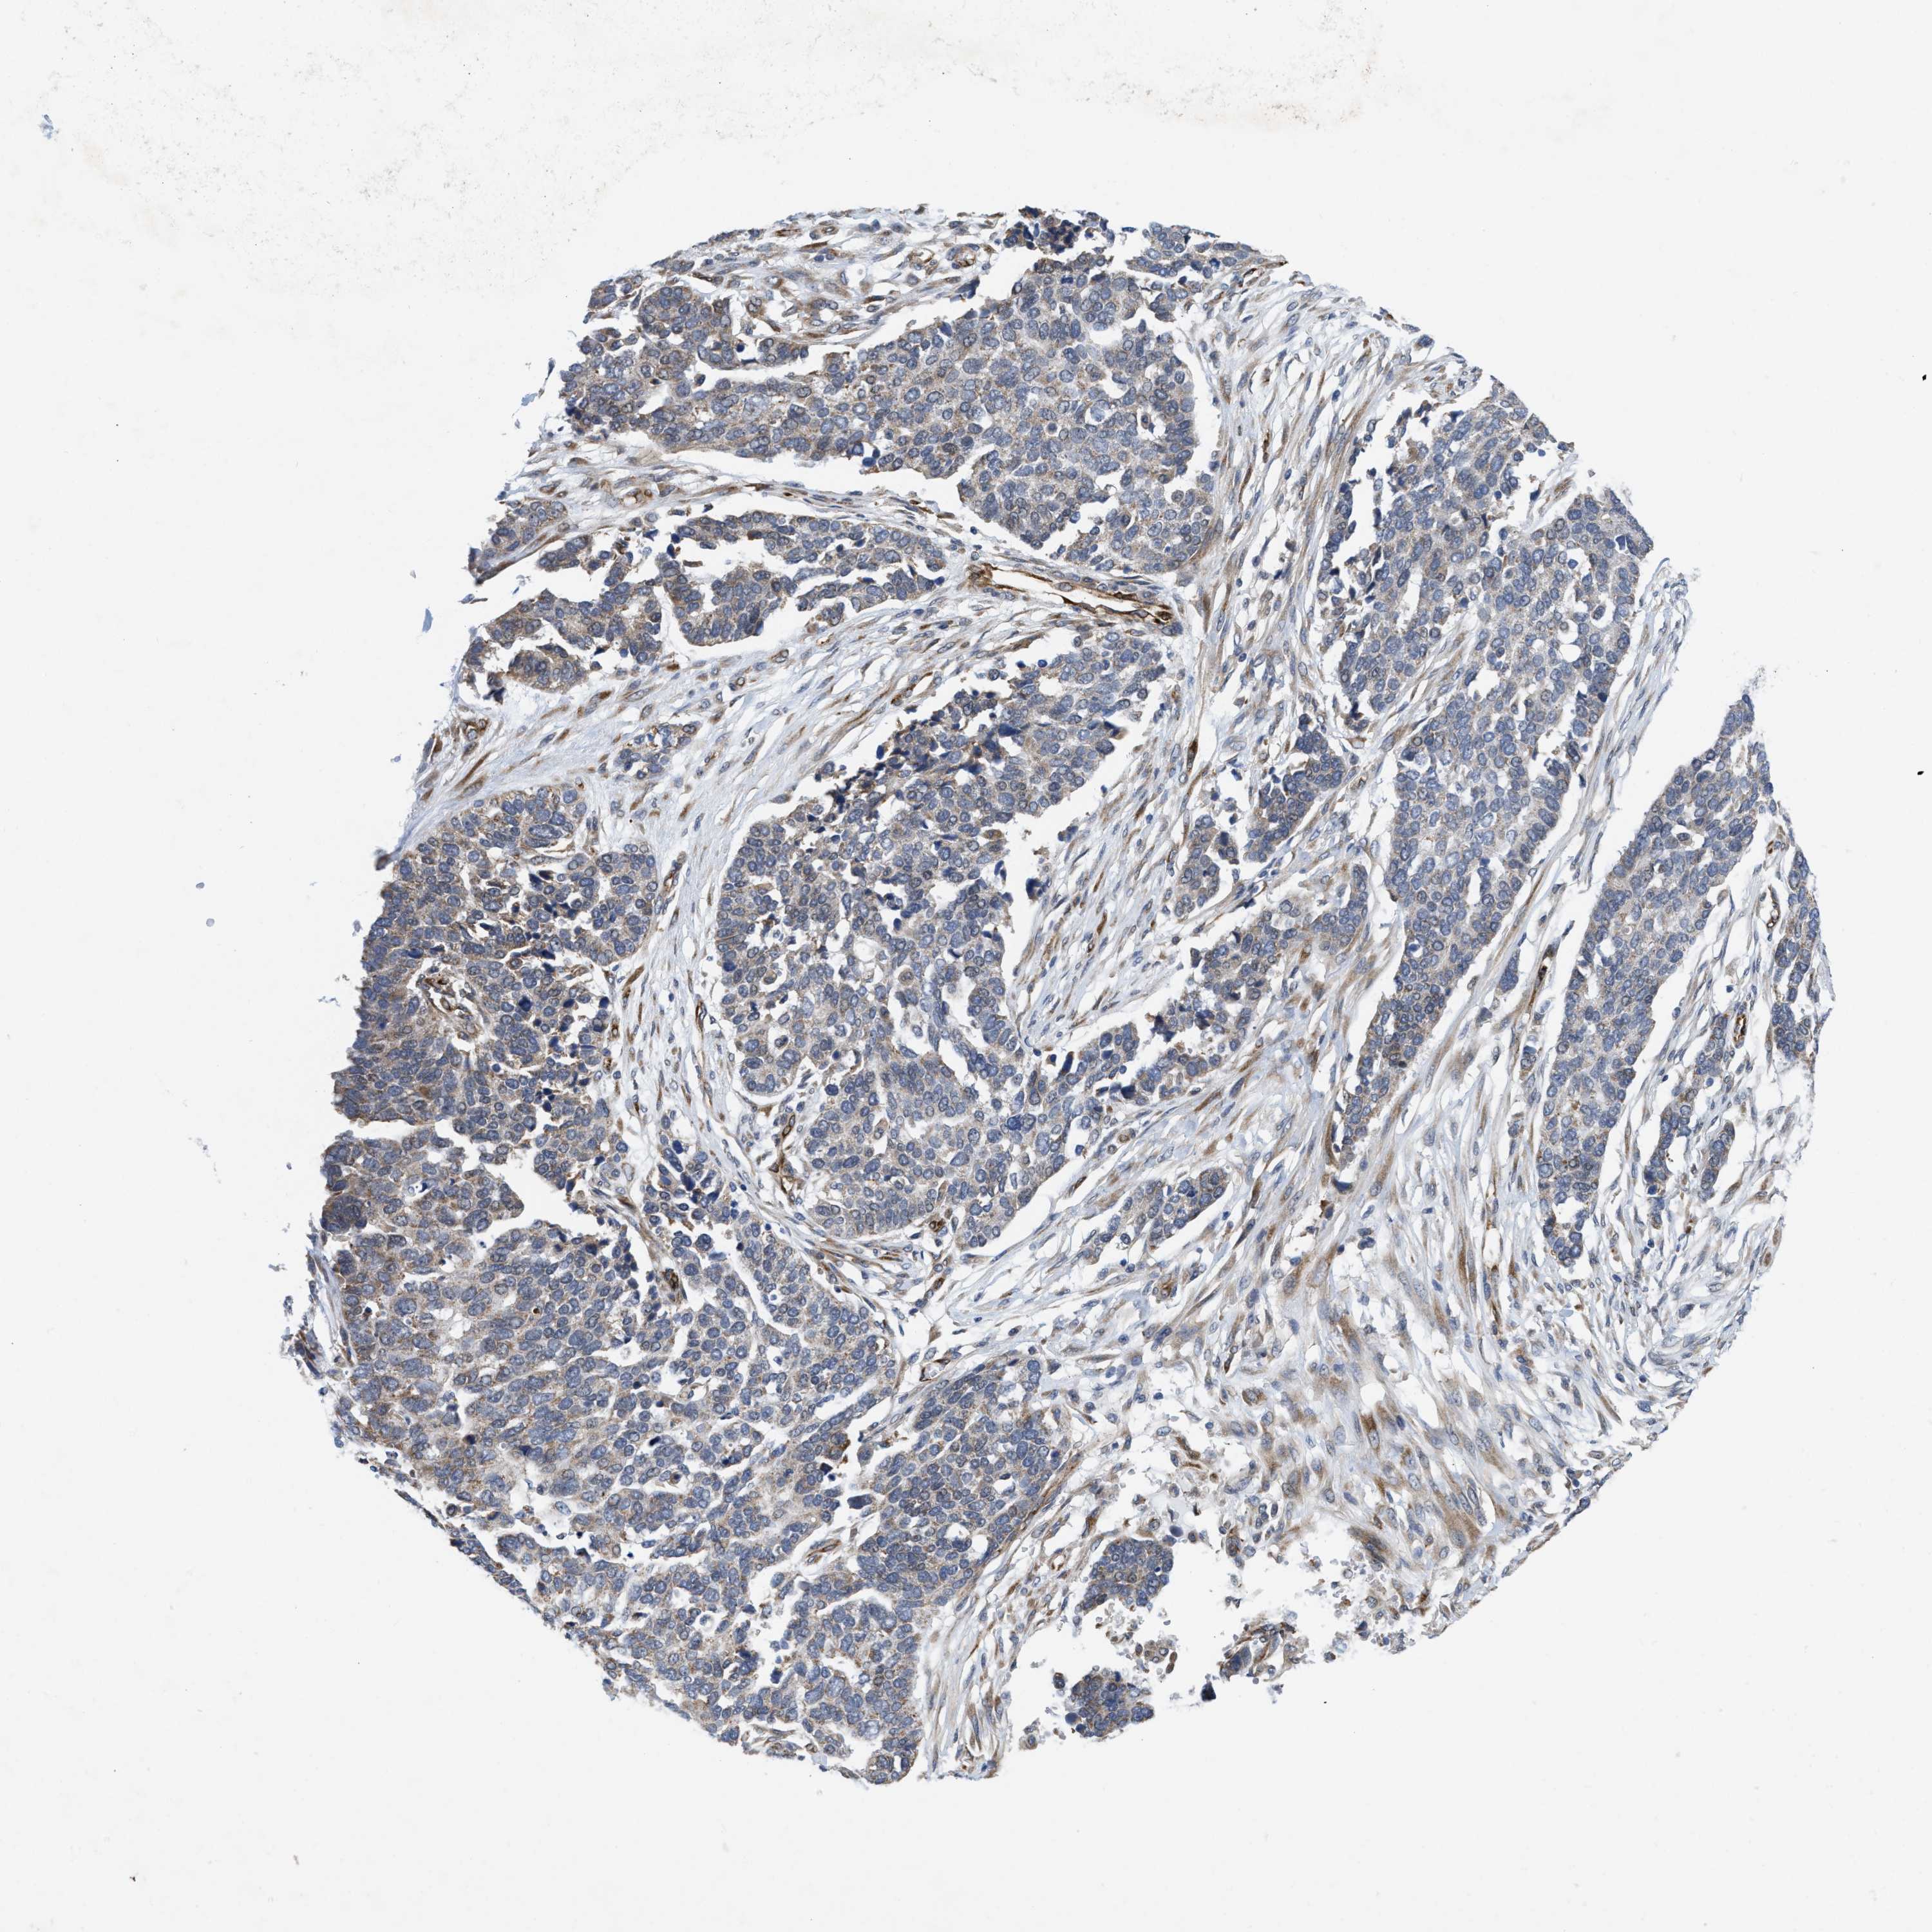

OVARIAN CANCER - Protein expressioni

A mouse-over function shows sample information and annotation data. Click on an image to view it in a full screen mode. Samples can be filtered based on level of antibody staining by selecting one or several of the following categories: high, medium, low and not detected. The assay and annotation is described here.

Note that samples used for immunohistochemistry by the Human Protein Atlas do not correspond to samples in the TCGA dataset.

Antibody stainingi

Antibody staining in the annotated cell types in the current human tissue is reported as not detected, low, medium, or high, based on conventional immunohistochemistry profiling in selected tissues. This score is based on the combination of the staining intensity and fraction of stained cells.

Each image is clickable and will lead to virtual microscopy that enables deeper exploration of all samples and also displays staining intensity scores, fraction scores and subcellular localization as well as patient and tissue information for each sample.

Antibody HPA019460

Staining

High

Medium

Low

Not detected

Intensity

Strong

Moderate

Weak

Negative

Quantity

>75%

75%-25%

<25%

None

Location

Nuclear

Cytoplasmic/membranous

Cytoplasmic/membranous,nuclear

Cystadenocarcinoma, serous, NOS

Carcinoma, endometroid

Cystadenocarcinoma, mucinous, NOS

Carcinoma, NOS